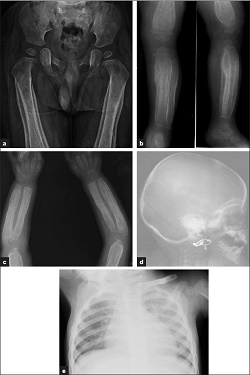

- Estudio del esqueleto. Una serie de radiografías que observan los huesos mayores en el cuerpo. Incluye el cráneo, brazos, piernas, costillas, columna, pelvis, manos y pies. Estas radiografías buscan cualquier problema en los huesos de su hijo. El número de radiografías dependerá de la edad del niño. Probablemente su hijo necesitará una segunda ronda en 3 semanas. El personal de Programación Central lo puede ayudar a hacer esta cita.

Se podría necesitar realizar imágenes (radiografías). Algunos padres se preocupan sobre los posibles efectos negativos de la radiación de las radiografías. El pequeño riesgo de radiación se compensa en gran medida por la información obtenida. El equipo especial y la manera de tomar radiografías aseguran que la exposición a la radiación sea lo más baja posible. Las imágenes de resonancia magnética no usan radiación.